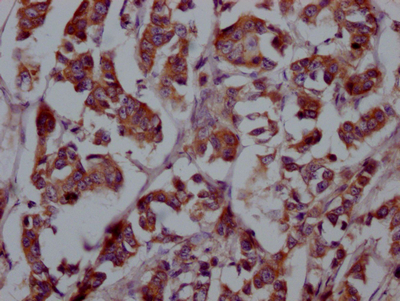

IHC image of CSB-RA927449A0HU diluted at 1:100 and staining in paraffin-embedded human breast cancer performed on a Leica BondTM system. After dewaxing and hydration, antigen retrieval was mediated by high pressure in a citrate buffer (pH 6.0). Section was blocked with 10% normal goat serum 30min at RT. Then primary antibody (1% BSA) was incubated at 4℃ overnight. The primary is detected by a Goat anti-rabbit IgG polymer labeled by HRP and visualized using 0.05% DAB.